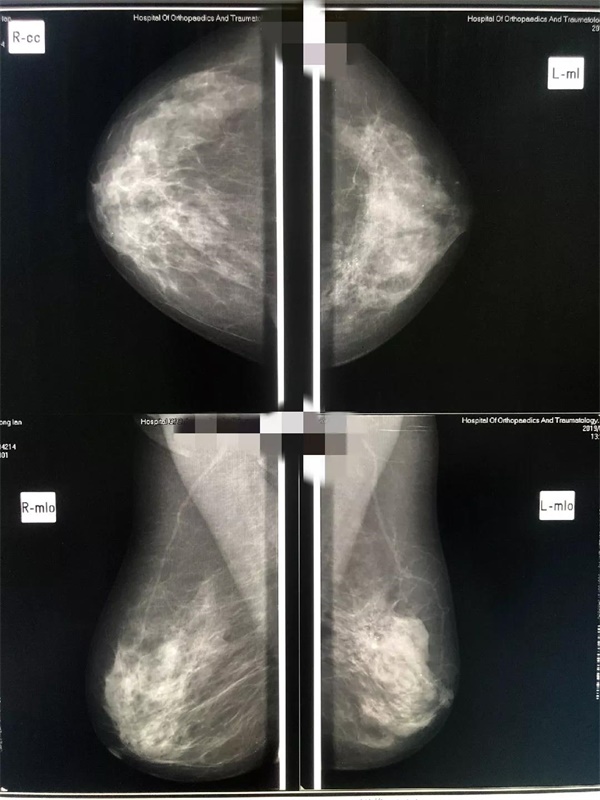

隨著生活水平的提高,乳腺癌的發(fā)病率越來越高,而且有年輕化的趨勢,已成為女性健康的一大殺手,所以,乳腺疾病的早發(fā)現(xiàn)、早診斷、早治療對保護女性健康具有十分重要的意義。

遼陽二院放射科乳腺鉬靶檢查設備先進,由放射科科主任劉曉威主檢,

診斷精準,服務熱情。

關(guān)愛女性健康從關(guān)愛乳腺做起

鉬靶檢查為女性健康保駕護航